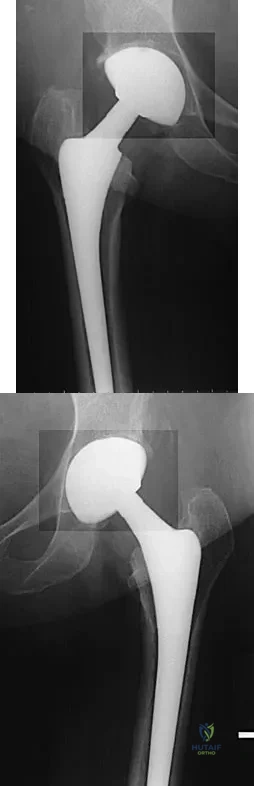

Question 93

A 68-year-old woman underwent a successful total right hip arthroplasty with a metal-on-metal articulation and cementless porous-coated components. Three months later, she underwent identical surgery on the left hip. Three months after surgery on the left hip, she reports groin pain on ambulation. Examination reveals significant groin discomfort with passive hip motion, particularly at the extremes of motion. Radiographs are shown in Figures 21a and 21b. Laboratory studies show an erythrocyte sedimentation rate of 35 mm/h and a C-reactive protein of 0.9. Aspiration yields scant growth of Staphylococcus epidermidis in the broth only, with no evidence of loosening on arthrography. A second aspiration yields scant growth of Staphylococcus epidermidis in the broth only. What is the most likely cause of the patient's pain?

Explanation